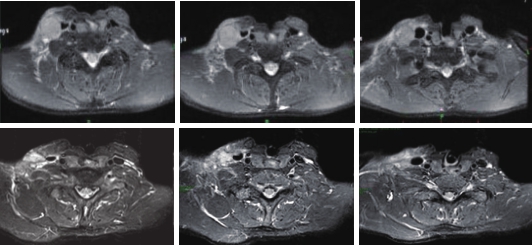

2018-11-21开始改行安罗替尼治疗(12mg/d,服用2周停1周),患者用药后病灶明显缩小,局部皮肤红肿疼痛好转(图2),复查MRI提示肿块明显缩小。服用2周期后,经MDT讨论,拟停药2周后行手术治疗。

图2 口服安罗替尼1周期后包块明显缩小,皮肤红肿消退

疗效评估:患者口服安罗替尼1周期后疗效评估达PR(图3),术后放疗后疗效为CR,随访至今,病情维持CR状态,局部MRI及全身检查未见肿瘤复发转移,无病生存时间已达30个月以上(图4)。

图3 口服安罗替尼2周期后疗效达PR